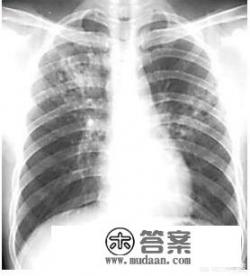

文字的描述很苍白,直接上图,正常的和肺结核的肺对比。如下:

这个图片,看到空洞了没,这就是结核的空洞,空洞里住着成千上万的结核分枝杆菌。

这个图片是上肺,相对正常的。一对比,就知道肺结核分枝杆菌对于肺结构的破坏力之大,破坏了你的肺,还不告诉你,甚至你完全不知道发生了什么,直到医生告诉你,做个肺ct吧,一扫就发现是上面那个样子。